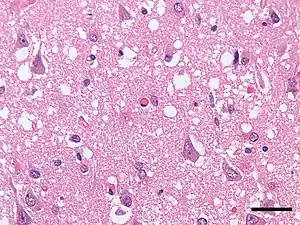

Micrograph showing spongiform degeneration (vacuoles that appear as holes in tissue sections) in the cerebral cortex of a patient who had died of a prion disease (Creutzfeldt-Jakob disease). H&E stain. Scale bar = 30 microns (0.03 mm). | |

Prions cause neurodegenerative disease by aggregating extracellularly within the central nervous system to form plaques known as amyloids, which disrupt the normal tissue structure. This disruption is characterized by "holes" in the tissue with resultant spongy architecture due to the vacuole formation in the neurons.[66] Other histological changes include astrogliosis and the absence of an inflammatory reaction.[67] While the incubation period for prion diseases is relatively long (5 to 20 years), once symptoms appear the disease progresses rapidly, leading to brain damage and death.[68] Neurodegenerative symptoms can include convulsions, dementia, ataxia (balance and coordination dysfunction), and behavioural or personality changes.